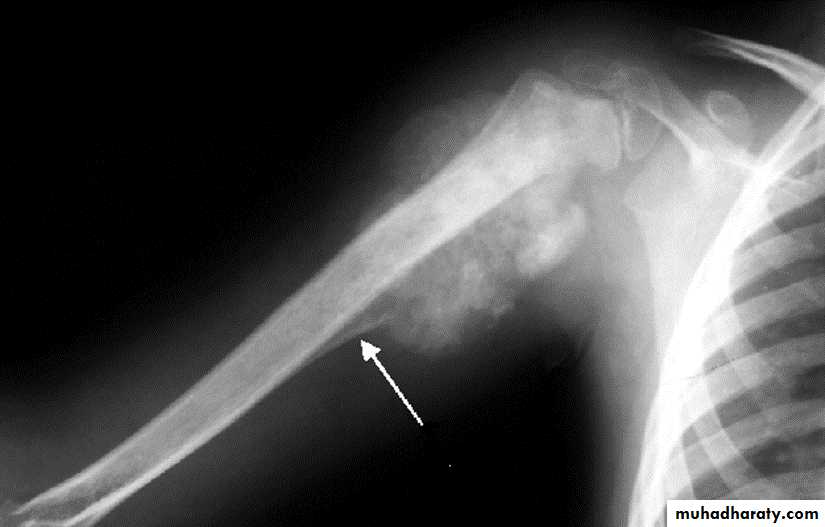

Area of bone destruction or sclerosis with ill-defined margins, wide zone of transition & periosteal reaction with or without cortical destruction & soft tissue swelling.Osteosarcoma :

Age: 5-20-yrs, elderly with Paget's disease.Site: metaphyseal around the knee joint.

Findings:

Lytic

Blastic

Mixed

Poorly defined bony destruction.

Sun ray speculation (periosteal reaction).

Elevation of the periosteum at the margin producing the so called Codman's triangle.

Cortical destruction.

Soft tissue swelling.